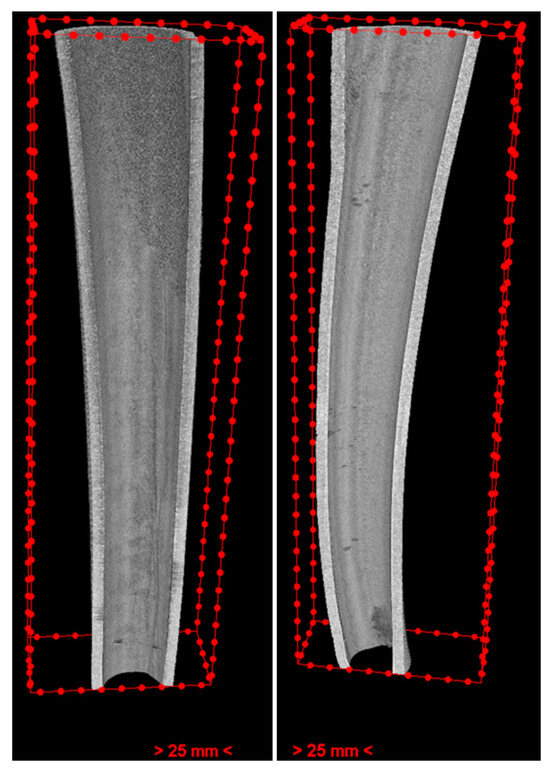

2.5. 3D Measurements

VGStudio MAX 2.1 (Volume Graphics GmbH, Heidelberg, Germany) was used to select the region of interest (ROI) and reference region in all data generated from SkyScan NRecon. It was used in all roots, including EDTA and HEDP groups as well as control groups. The ROI, a sleeve with a depth of 50 voxels around the root canal, was selected to calculate erosion. The reference region consisted of a sleeve with a 50-voxel depth above the inner sleeve. (Figure 2) For image processing and to obtain density curves for each tooth, Python (Version 3.11.2, Python Software Foundation) was applied.

Figure 2. One layer of the selected ROI (left) and the reference region (right) in the EDTA case root.